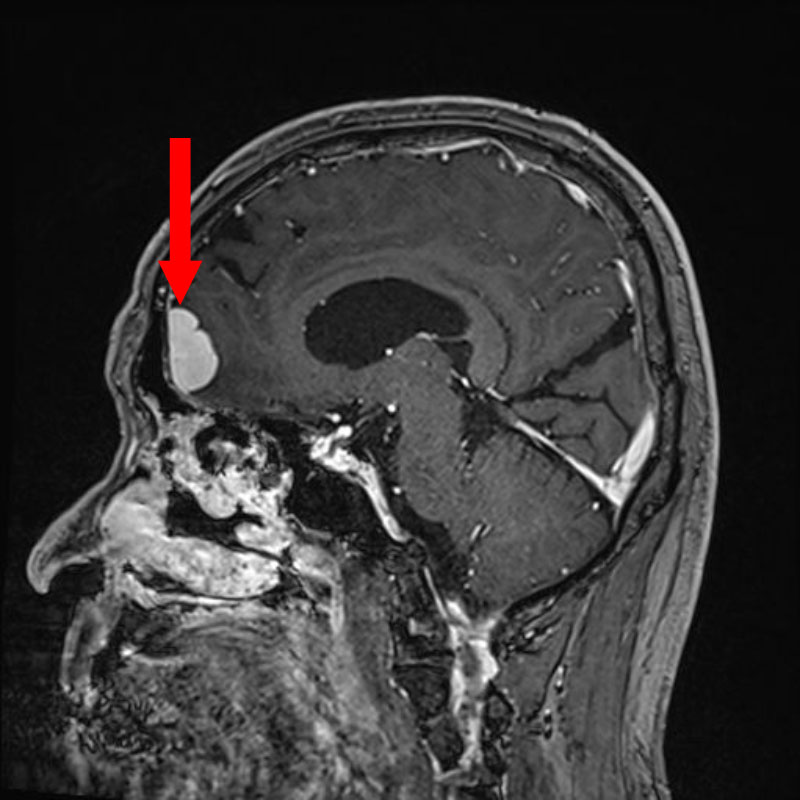

629

'25年5月

50代

円蓋部髄膜腫

頭蓋内腫瘍摘出術